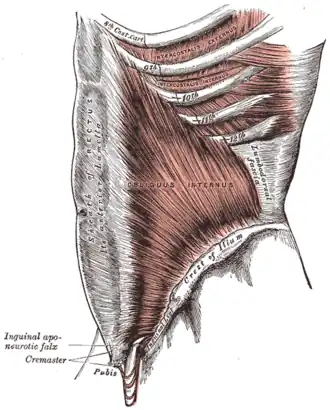

The rectus sheath (extensive vertical darker gray at left), an example of a fascia | |

A fascia (/ˈfæʃ(i)ə/; pl.: fasciae /ˈfæʃii/ or fascias;[1] adjective fascial; from Latin band) is a generic term for macroscopic membranous bodily structures.[2]: 42 Fasciae are classified as superficial, visceral or deep, and further designated according to their anatomical location.[3]

Deep fascia is a layer of dense fibrous connective tissue which surrounds individual muscles and divides groups of muscles into fascial compartments. This fascia has a high density of elastin fibre that determines its extensibility or resilience.[19] Deep fascia was originally considered to be essentially avascular but later investigations have confirmed a rich presence of thin blood vessels.[20] Deep fascia is also richly supplied with sensory receptors.[21] Examples of deep fascia are fascia lata, fascia cruris, brachial fascia, plantar fascia, thoracolumbar fascia and Buck's fascia.